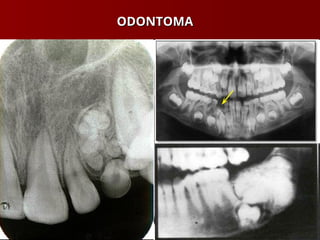

 Odontoma

ODONTOMA

TUMORES ODONTOGÊNICOS TUMORES ODONTOGÊNICOS Ameloblastoma Ameloblastoma  Cementoma – Displasia Cementossea Cementoma – Displasia Cementossea Focal Focal  Odontoma Odontoma